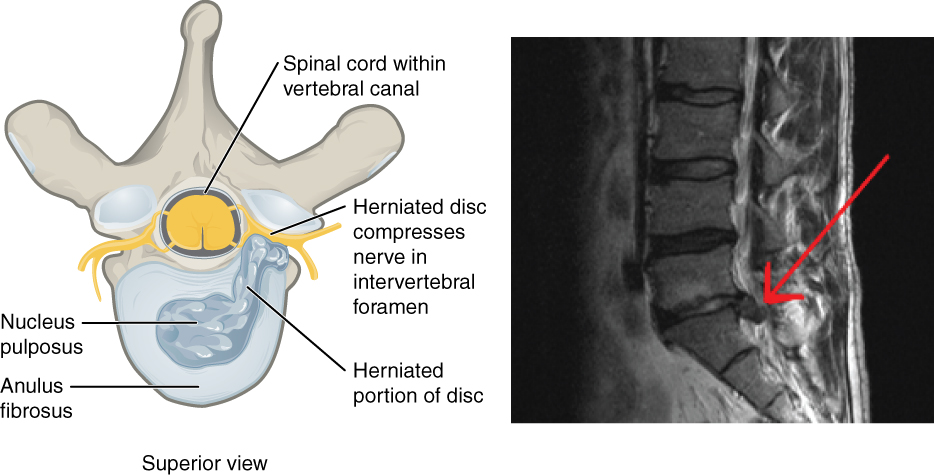

Diagnosis of Herniated Discs

Diagnosing a herniated disc typically involves a combination of physical examinations, imaging tests, and patient history. Healthcare providers will often begin with a comprehensive physical exam, assessing the range of motion, reflexes, and areas of tenderness. Following this, imaging techniques such as X-rays, MRIs, or CT scans may be utilized to visualize the spine and identify any disc protrusions. In some cases, doctors may also use electromyography (EMG) to assess nerve function. Research indicates that MRIs are particularly effective in diagnosing herniated discs, with an accuracy rate of over 90%. It’s important to understand that while imaging can pinpoint the presence of a herniated disc, it does not always correlate with the severity of symptoms. Many individuals with herniated discs lead active lives without requiring surgical intervention, emphasizing the need for a personalized approach to diagnosis and treatment.